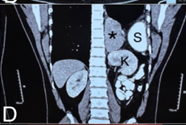

Congenital diaphragmatic hernia (CDH) is a birth defect involving improper formation of the diaphragm, leading to the protrusion of abdominal organs into the chest cavity. The CDH is classified depending on the location of the defect as postero-lateral, central and anterior. Depending on the side, it is classified as right, left and bilateral. A majority of CDH defects are postero-lateral defects and are commonly referred to as Bochdalek hernias (BH). Herein, the authors present the case of a 29 years old male patient diagnosed with a large left recurrent Bochdalek hernia. He was operated for it in another hospital by another surgeon 5 months back. That previous surgical intervention was initially planned via laparoscopy. But, intraoperatively, it had to be converted to open surgery due to technical difficulty. Post the first surgery, after about 1.5 months, he started developing pain in the back of his left chest. However, due to financial constraints, he did not seek any consultation with anyone at that time. The authors successfully performed a laparoscopic repair of this difficult condition. The rationale for reporting this case is to underscore the relative ease of a laparoscopic over open surgical intervention, on the ‘roof’ of the abdomen and also the lower chest. Also, it hopes to highlight that laparoscopic repair of BH is feasible even in challenging, difficult and recurrent scenarios, in an advanced setup backed up by the requisite surgical expertise.